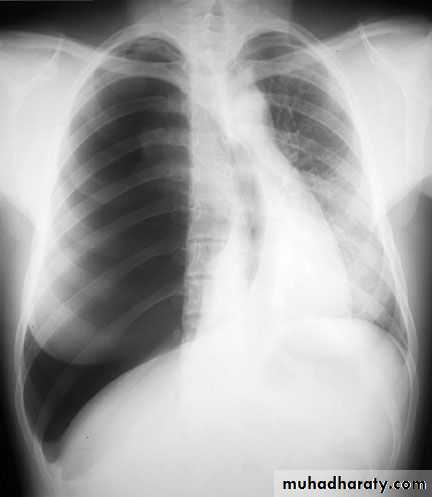

Massive right effusion

X-ray hemothorax

X-ray pneumohemothorax